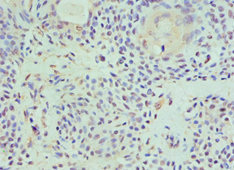

Immunohistochemistry of paraffin-embedded human breast cancer using CSB-PA010143ESR2HU at dilution of 1:100

Immunohistochemistry of paraffin-embedded human colon cancer using CSB-PA010143ESR2HU at dilution of 1:100